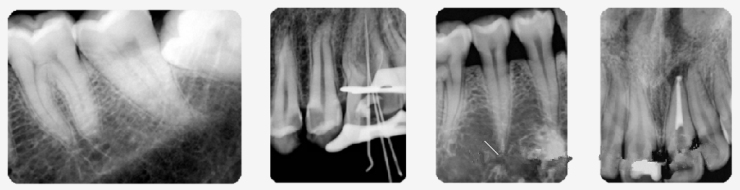

年度新品Smart3D-X三合一智能口腔CBCT即将在磴口县人民医院投入运用,它将CT、全景、头颅和口内摄影(牙片)四种功能集合于一体,可满足各类口腔患者口腔X射线影像拍摄需求,做出精准诊断。现已面向口腔患者开启种植检查预约,并开通种植牙职工医保报销。

准确扫描种植部位 避免其他损伤